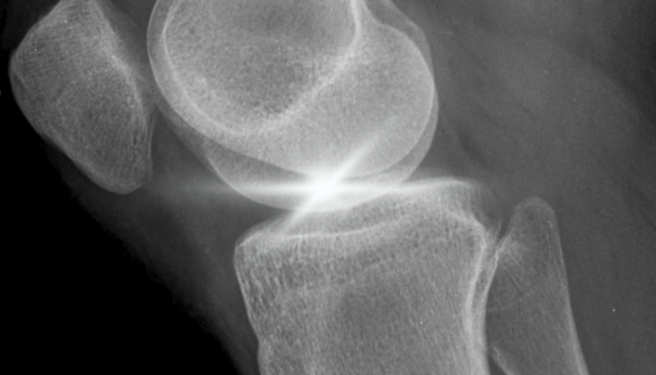

The surface of osteoarthritic cartilage is characterized by profound alterations in both composition and topography: proteoglycan depletion reduces interstitial osmotic pressure, while exposure of collagen fibrils increases roughness and modifies surface charge distribution. In this scenario, functionalized fibroin-based systems show a significant advantage in terms of adhesion and persistence.